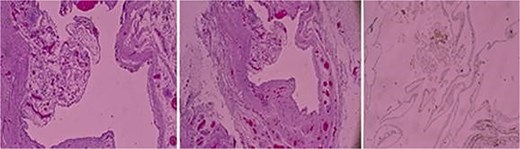

A right inguinal exploration was performed under general anesthesia. A cystic structure consistent with a canal of Nuck cyst was identified within the inguinal canal (Fig. 2). Dissection was performed around the cyst until it was completely released. The cyst was excised in its entirety and sent for histopathological analysis that confirmed the diagnosis of a benign cyst lined with mesothelial cells and containing serous fluid, consistent with a canal of Nuck cyst (Fig. 3). Postoperatively, the patient recovered well, tolerated her diet, ambulated independently, and maintained clean dressings.